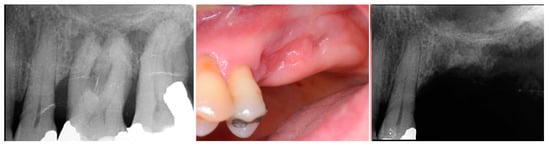

A 54-year-old female patient presented with loss of crowns on the upper left 1st and 2nd maxillary molars that had previous endodontic treatment. Examination noted minimal coronal tooth structure remaining and significant bone loss between the two molars with probing of over 10 mm. A periapical radiograph was obtained and confirmation of the poor condition of the two molars both structurally and periodontally was noted (Figure 1, left). Treatment options were discussed with the patient who wished a fixed approach. It was recommended that the two failing molars be extracted, and socket grafting be performed to create a crestal base to support an implant following site healing. At a subsequent surgery, a crestal sinus augmentation would be performed with simultaneous implant placement. This would then be allowed to heal before restoration of the implant at the 1st molar site was initiated.

Figure 1.

Failing endodontically treated 1st and 2nd molars (left), socket grafting with EthOss at time of extraction (middle) and following 10 weeks of healing demonstrating increased ridge height for implant placement with simultaneous crestal sinus augmentation (right).

The consent form was reviewed with the patient and then signed. Local anesthetic was administered into the buccal vestibule adjacent to the molars to be treated. The two molars were atraumatically extracted, and the sockets were curetted to remove any residual tissue. The EthOss graft material syringe was held vertically and per the manufacturer’s instructions, sterile saline was added to the syringe to wet the graft material. Once the saline had wetted the graft material, the end cap was removed from the syringe and a piece of dry gauze was utilized to remove any excess saline. The syringe was then carried to the intraoral site and expressed into the sockets. The material was gently compressed to shape it to fill the void being grafted with sterile gauze for 3 min at which stage it began to harden, showing resistance to pressure and being firm to touch. The flap margins were then closed to achieve primary closure and secured with 5–0 PGA sutured in an interrupted fashion. A periapical radiograph was obtained to document the socket grafting (Figure 1, middle).

The patient returned at 10 weeks post-surgery and a periapical radiograph was obtained to evaluate the graft healing (Figure 1, right). The graft was noted to have blended with the surrounding host bone and was deemed ready for implant placement. The soft tissue covering the grafted portion of the ridge was keratinized and no inflammation was noted (Figure 2). Local anesthetic was again administered in a similar manner as the previous surgery. A crestal incision was made from the distal of the distal papilla at the 2nd premolar to a point where the 1st molar would be positioned. A releasing incision was made at the distal of the papilla and also at the posterior extent of the crestal incision and extended into the buccal vestibule. A full-thickness flap was elevated to expose the crestal ridge (Figure 3). The graft had converted to bone at the extraction sockets. A pilot drill was utilized to start the osteotomy to a depth of 4 mm, 2 mm shy of the sinus floor as measured on the radiograph. The osteotomy was increased laterally utilizing Densah osseodensification burs (Versah, Jackson, MI, USA) to a width of 4 mm (Figure 4, left). EthOss graft material that had been hydrated in the syringe was dispensed into the osteotomy and the final Densah bur was utilized to elevate the sinus floor and laterally spread the graft material to gain height for the implant placement (Figure 4, right). A 5 mm × 8 mm Paltop Addvanced (Paltop, Cesarea, Israel) implant was introduced into the site to the desired crestal depth (Figure 5, left). A cover screw was placed, and additional EthOss graft material was placed at the crest to fill a depression on the distal aspect adjacent to the implant (Figure 5, middle). A periapical radiograph was obtained to document the implant and associated sinus/crestal grafting performed at this stage (Figure 5, right).